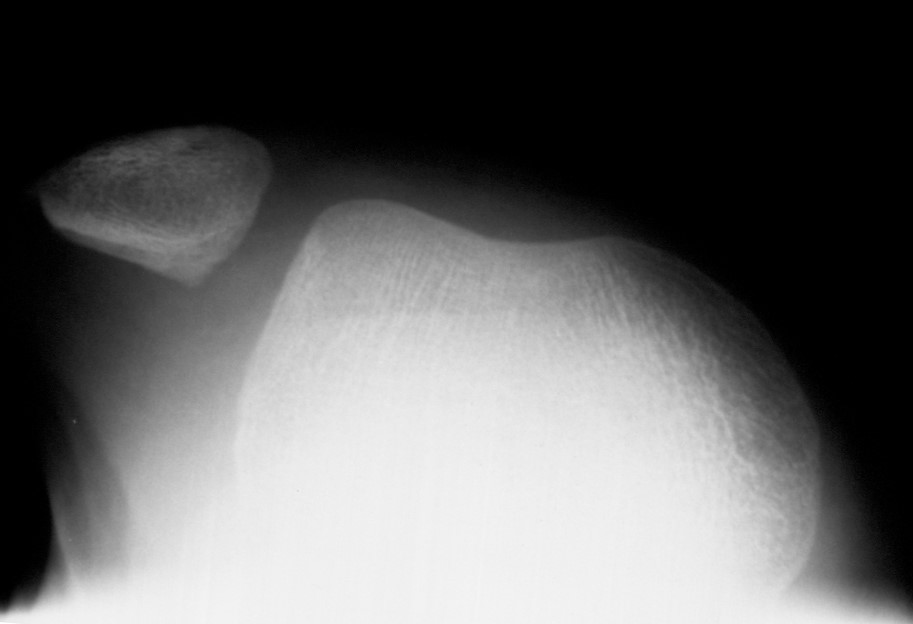

レントゲンで膝蓋骨が脱臼していることがわかります

膝をひねった時に膝蓋骨(おさらの骨)が大腿骨からはずれる(脱臼)ことを膝蓋骨脱臼と言います。脱臼する頻度は人によって異なります。脱臼しやすい原因がたくさんある人は不安感が強く普段の生活でも脱臼することがあります。脱臼を繰り返すと膝の軟骨が損傷し骨が変形することがあります。